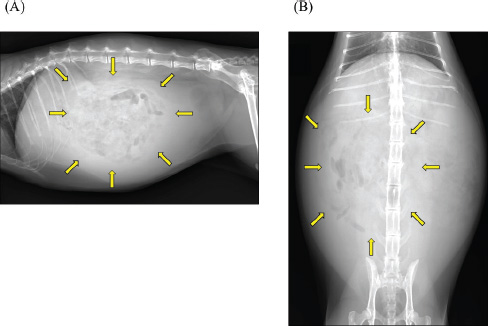

A 2-year-old castrated male domestic shorthair cat, weighing 5.3 kg, presented with a 2-month history of abdominal distension and a 4-day history of anorexia. There was no history of illness or abdominal surgery. Physical examination revealed severe abdominal distension with a fluid wave and mild hypothermia (37.1°C). Blood tests revealed mild elevations in blood glucose (178 mg/dl; reference interval 71–148 mg/dl) and serum amyloid A (5.27 µg/ml; reference interval <3.75 µg/ml) levels, while lipase activity was within normal limits (23.9 U/l; reference interval <30 U/l). Abdominal radiography revealed increased radiopacity and digestive tract consolidation (Fig. 1). Abdominal ultrasonography revealed severe ascites, small intestine hypoperistalsis, pancreatic enlargement, and irregular thickening of the peritoneum with several nodules (Fig. 2). Echocardiography revealed no abnormality. In the ascitic fluid analysis, the total nucleated cell count was 1,000 cells/μl with no evidence of neoplastic cells or bacterial infection, and the specific gravity of the supernatant was 1.024, confirming the ascites as a modified transudate (Fig. 3). Feline infectious peritonitis was considered unlikely due to the absence of feline coronavirus genes in the ascitic fluid and no elevation in blood anti-coronavirus antibody titers. Based on the imaging findings, such as peritoneal thickening, gastrointestinal tract consolidation, and severe ascites, EPS was initially suspected. These findings are consistent with the typical presentation of EPS, characterized by fibrotic thickening of the peritoneum and encasement of abdominal organs (Gremillet et al., 2022). However, the possibility of malignancy was deemed unlikely due to the cat’s relatively young age. A trial treatment with prednisolone (10 mg/head, q24 h) and enrofloxacin (25 mg/head, q24 h) was initiated to manage the suspected inflammatory process and potential bacterial infection, respectively. However, no clinical improvement was observed, suggesting that the underlying condition might be more complex than initially suspected. A non-sedated computed tomography (CT) scan was performed to obtain more detailed diagnostic information on day 12 after presentation. A Siwtenn-slice multi-slice CT scanner (Aquilion™ Lightning, Canon Medical Systems, Japan) was used without anesthesia, with the patient restrained in an acrylic cage (CT capsule, Terucom, Japan). The following technical parameters were used: rotation time=0.75 s; slice thickness=1 mm; reconstruction interval=0.5 mm; table speed=16 mm/rotation; helical pitch=16.0; X-ray tube voltage=120 kV; and X-ray tube current=100 mA. The CT scan revealed a tumor-like enlargement of the pancreas, irregular scattered nodular formations aggregating dorsally in the peritoneum, and ground-glass opacity in the right lower lobe of the lung (Fig. 4). Because angiography was not performed, the vascular characteristics and more detailed differentiation of the soft tissue masses could not be assessed. A pancreatic tumor was suspected; however, diagnostic and therapeutic surgical interventions were deemed difficult due to the animal’s condition. In addition, the owner declined further invasive procedures, such as fine-needle aspiration or laparoscopy. Despite prednisolone treatment (5 mg/head, 24 h), ascitic fluid drainage, and fluid therapy, the cat died 19 days after the first presentation.

Fig. 1. Abdominal radiographs. (A) Right lateral and (B) ventrodorsal radiographs are shown. The images show severe abdominal distension and a generalized decrease in contrast, suggesting ascites. Mild gas retention and clustering of the intestines were observed (arrow).